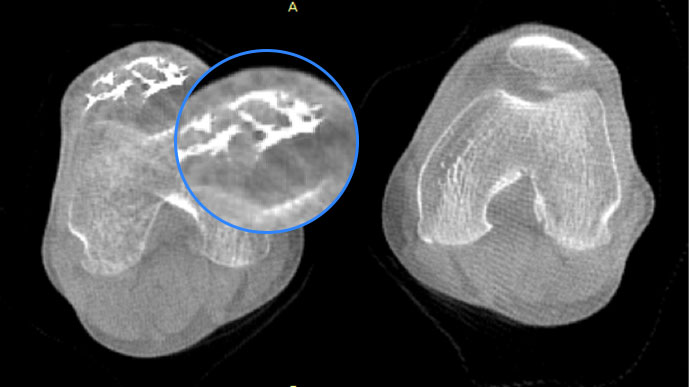

膝關節

關閉金屬偽影校正

開啟金屬偽影校正